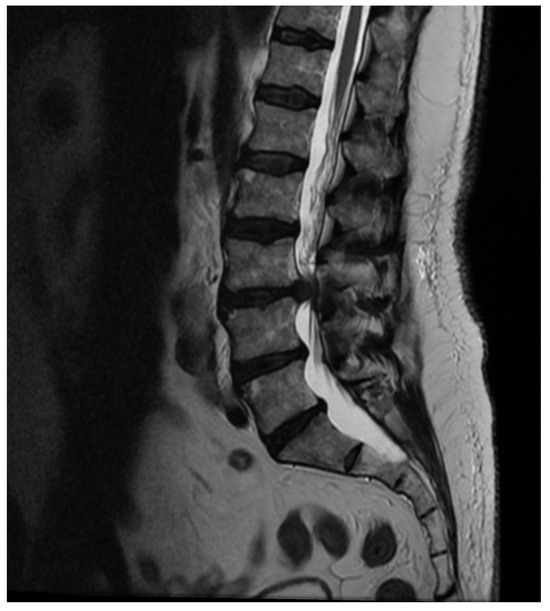

Patient Background: A 50-year-old female patient with a body mass index (BMI) of 32 was admitted to the neurology emergency department due to an acute spinal pain syndrome persisting for three days. The pain, VAS 7, was located in the lower spine, radiating bilaterally to both lower limbs, and exacerbated by movement. The patient had undergone a gynecological procedure under epidural anesthesia one month prior to this episode. Initial MRI (Figure 2) of the spine revealed a collapse of the L5/S1 space with a small central protrusion. The disc signal raised suspicion of early inflammatory changes in the eyes of the consulting neurosurgeon, though the radiologist conclusively denied inflammatory features. The patient presented with slightly elevated inflammatory markers, with a CRP level of 20 mg/L.

Diagnostic Evolution: After a week of conservative treatment without improvement, a follow-up MRI was ordered(Figure 3), which unambiguously identified spondylodiscitis with an abscess in the canal, causing compression of the dural sac and both S1 nerves (Figure 4). The patient’s pain syndrome worsened significantly, VAS 9 in the lower spine, leading to her qualification for surgical treatment.

Figure 2. Pre-operative T2 axial MRI image at the L5/S1 level on the day of the patient’s admission to the neurology department.

Figure 3. Pre-operative T2 sagittal MRI image at the L5/S1 level on the day of the patient’s admission to the neurology department.